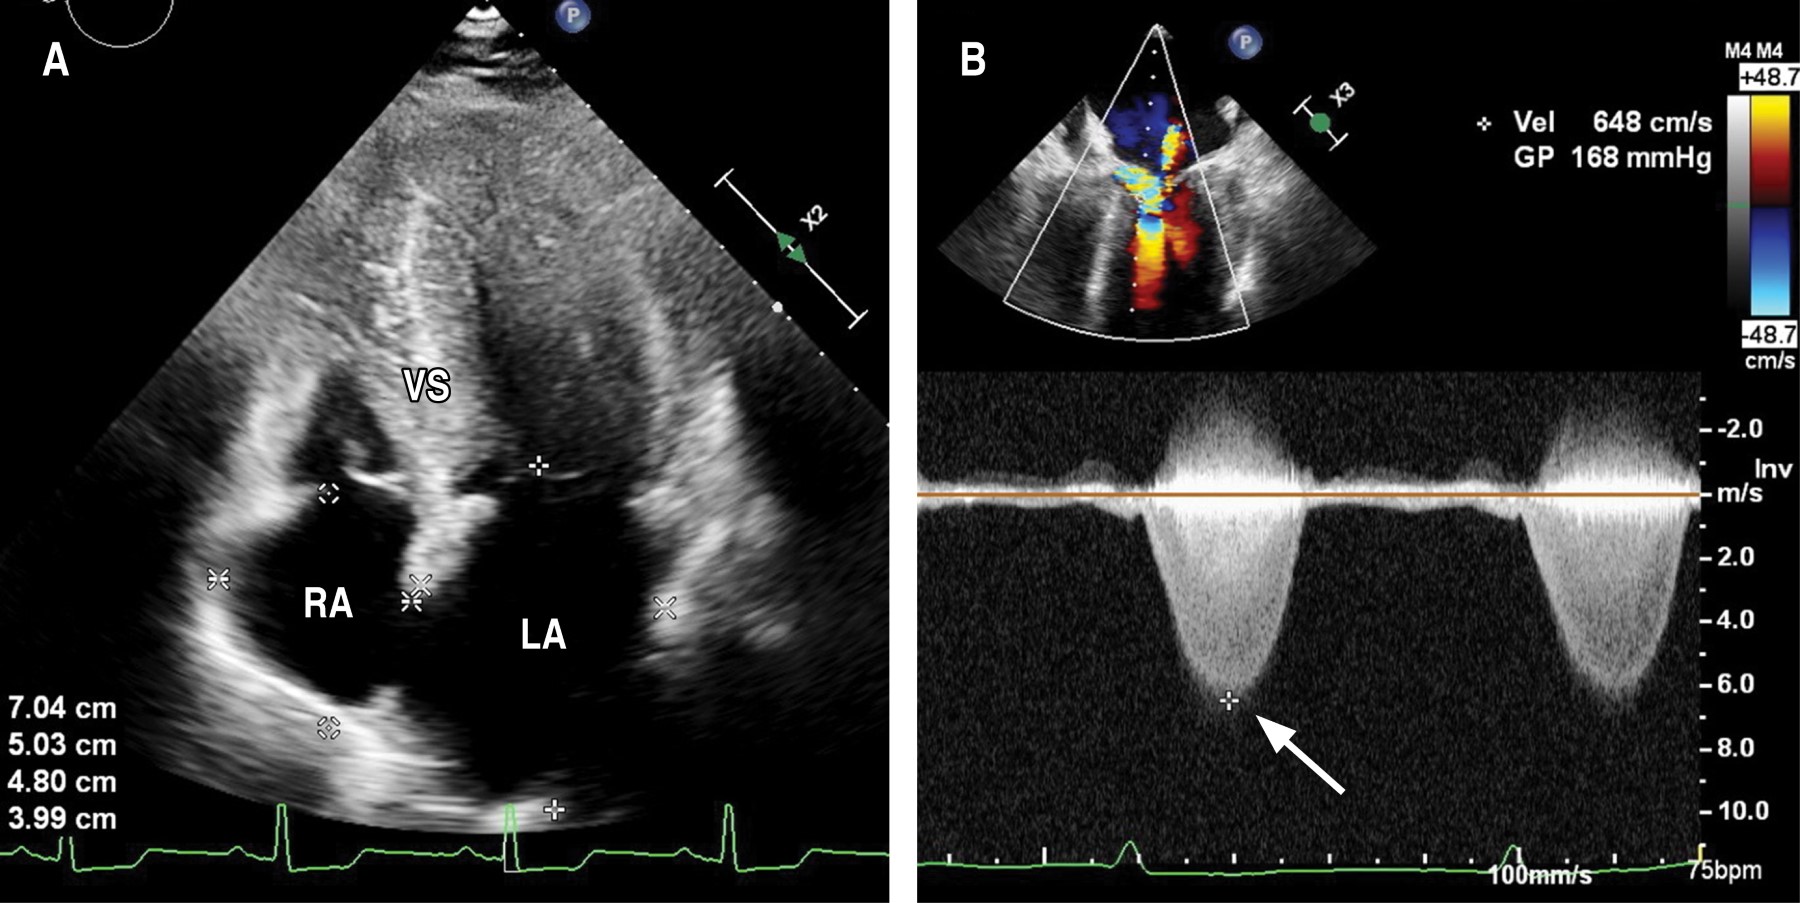

A transthoracic (TTE) and a transesophageal echocardiogram (TEE) were requested to determine the gradient site and assess the possibility of alcohol septal ablation. The TTE showed a predominantly anterior septal hypertrophy, with a maximum thickness of 27 mm; significant left atrial dilation, with an increased volume of 56 ml (Figure 2A); mitral valve sclerosis with calcification spots and mild-moderate mitral regurgitation. The TEE showed generalized low-grade hypokinesia, left ventricular ejection fraction (LVEF) of 64%, and an intraventricular gradient at rest greater than 168 mmHg, with an anterior systolic movement of the anterior mitral leaflet (Figure 2B).

Figure 2